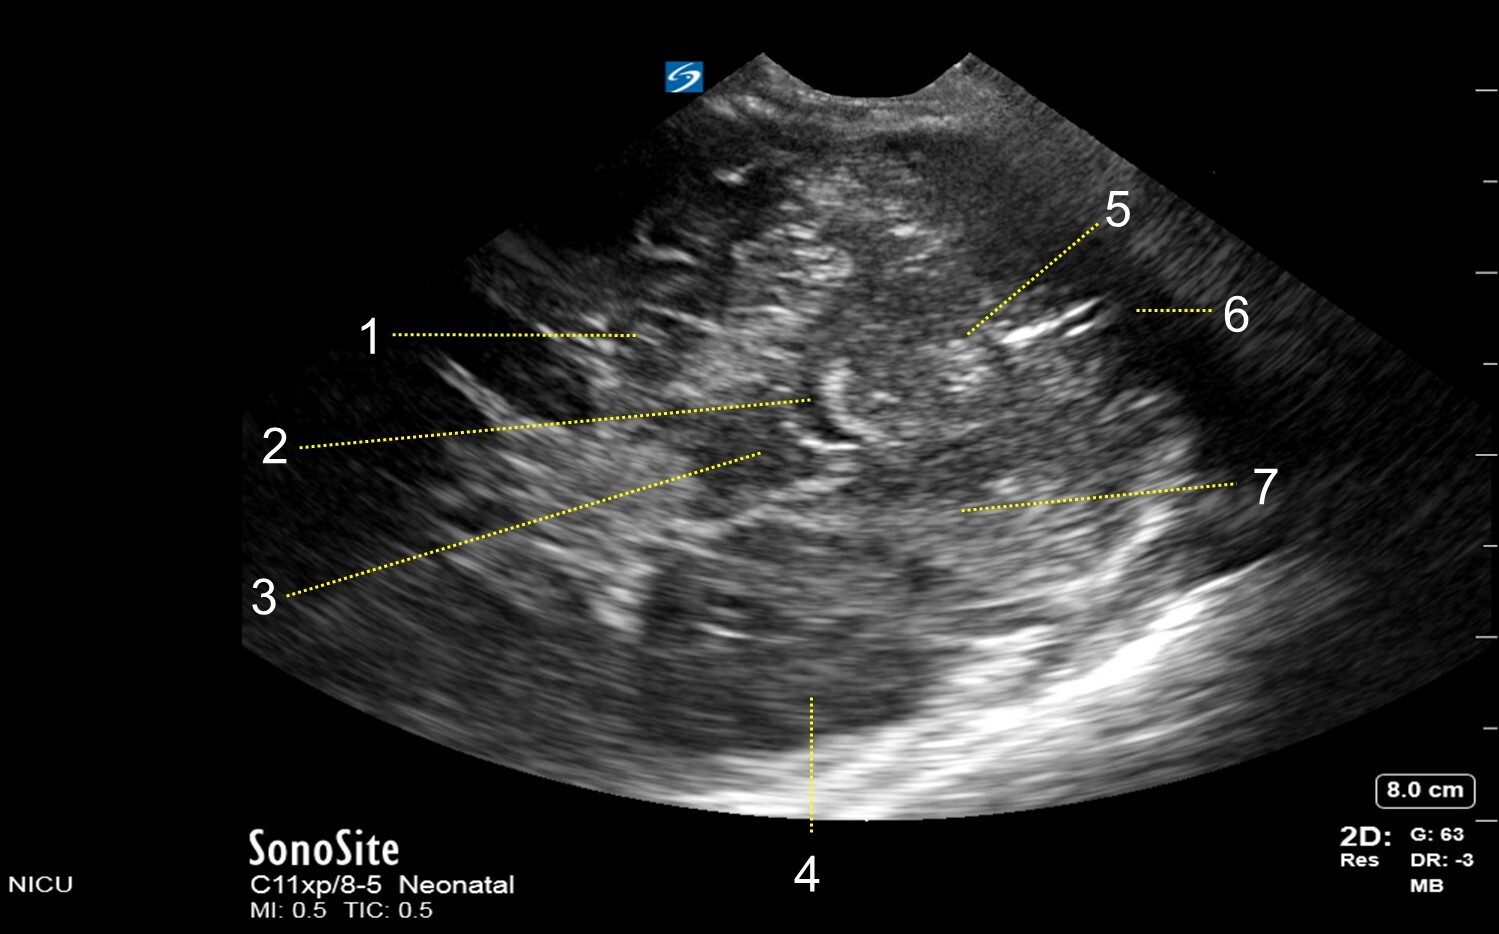

Neonatology Mastoid Fontanel – Mid-Transverse View Image

1. Temporal Horn of Lateral Ventricle

2. 4th Ventricle

3. Pons Temporal Lobe

4. Temporal Lobe

5. Cerebellar Vermis

6. Cisterna Magna

7. Cerebellar Hemisphere